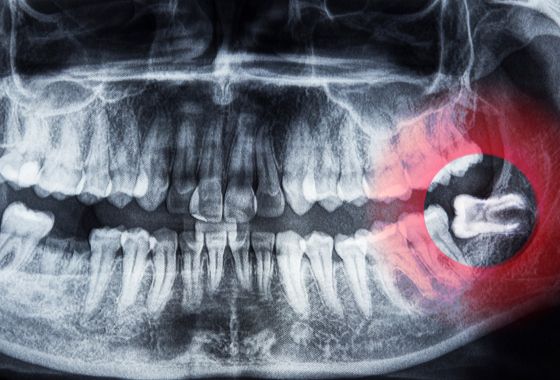

Cirugía de muelas de juicio

La cirugía de terceros molares es tan común en la silla dental, ya que son las muelas en ultimo de salir en nuestra boca y por lo regular vienen inclinadas o les falta espacio para que puedan caber en nuestra boca y esto contrae muchos problemas como:

- Dolor

- Infección

- Empaquetamiento de comida

- Quistes

- Caríes

Cirugía de muela de juicio

Desde $2300

(Se deberá realizar primero una valoración y toma de radiografía, no incluido en el precio)